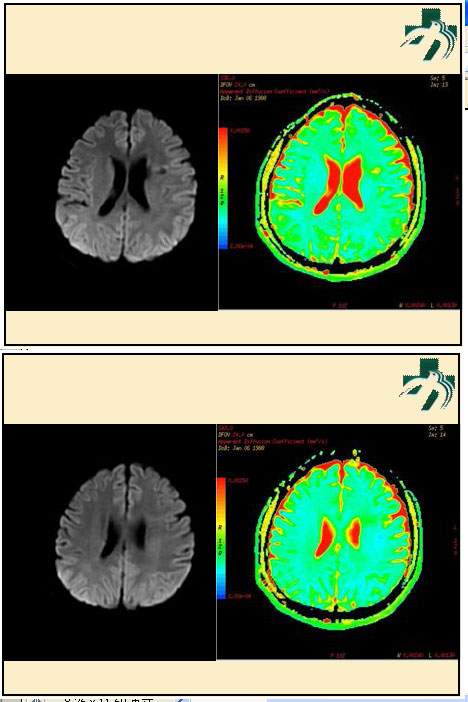

奴卡氏菌感染

第九期三博

读片会

病例之四

北京协和医院 提供

男性,22岁。自觉虫咬后皮疹、肢体麻木4月